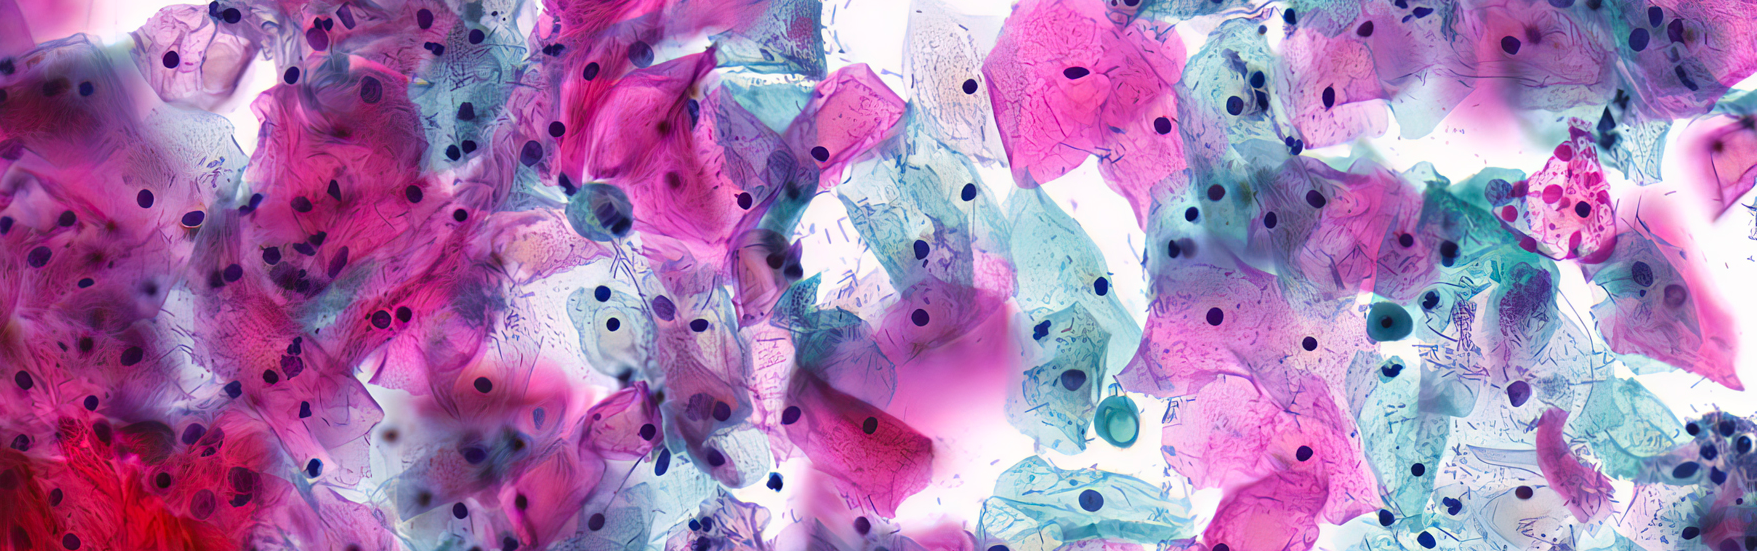

E-Leviate Pharma leverages proprietary, IP-protected technology to deliver cutting-edge solutions in drug delivery and biomedical innovation. The medical device from E-Leviate is designed to treat pelvic organ prolapse (POP) and urinary stress incontinence. Unlike conventional pressaries, it incorporates a sustained low-dose estriol delivery system.

E-leviate is tackling a “silent epidemic” of menopause-associated disorders that disproportionately impacts Māori and Pacific women, who face cultural, systemic and access barriers to care. Its world-first estriol-eluting pessary ring combines structural support with six months of local oestrogen delivery, replacing messy daily creams and frequent clinical visits.

Pelvic Organ Prolapse (POP) is a common condition affecting women globally, yet access to effective care remains unequal. Symptoms like bleeding and urinary incontinence can significantly impact daily life and wellbeing. Limited access to care, alongside disempowering or culturally unsafe experiences, creates emotional, cultural, and financial burdens—particularly for Māori and Pasifika women—and contributes to poorer health outcomes. E-Leviate addresses this gap with a pessary device that provides structural support and targeted oestrogen delivery. By reducing the need for frequent clinical visits and improving treatment adherence, it supports better outcomes while empowering patients and whānau to take greater control of their health.

E-Leviate fills a key gap in POP care: while pessaries are commonly used, no existing solution offers both structural support and targeted oestregen delivery. By simplifying care and reducing reliance on frequent appointments, it can improve outcomes and make it easier for priority communities to access and sustain treatment—especially where clinical access is constrained.